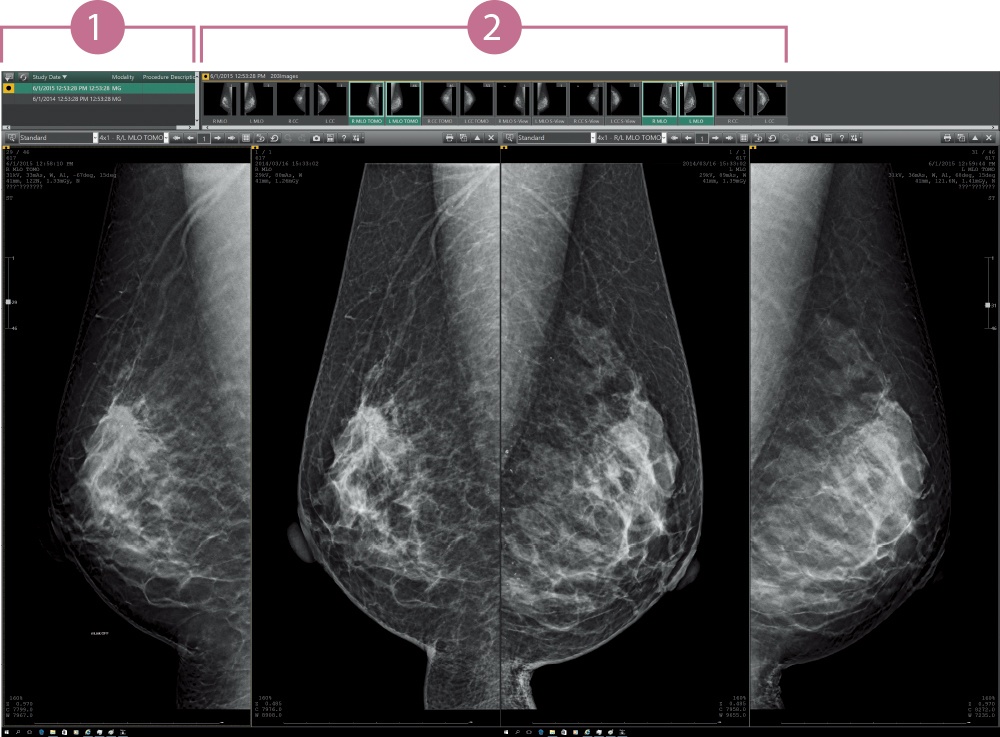

Support for users in conducting diagnosis with reading protocols tailored to mammographic diagnosis and smooth image displays. Customization for reading protocols includes configuration for making comparisons of current and prior images and for S-views synthesized from tomosynthesized images of AMULET Innovality and AMULET SOPHINITY.

The results from multiple exams for a patient are displayed in a list. Users can switch the displayed image with one of the selected images.

The thumbnail window allows users to instantly see all the images taken for each individual exam in a single one view. Each image can be easily selected and displayed by dragging and dropping.

Various images, such as MG, BT, MR, CT, US, etc., are available for mammography diagnosis at the same time.

Snapshot function: The display conditions, order, and scale factor of each image can be stored on the computer and re- displayed in the same condition.

Once a prescription format is stored, images of a patient from different exams can be arranged to be printed out with the measurement results in the preferred space and at the desired size and contrast.